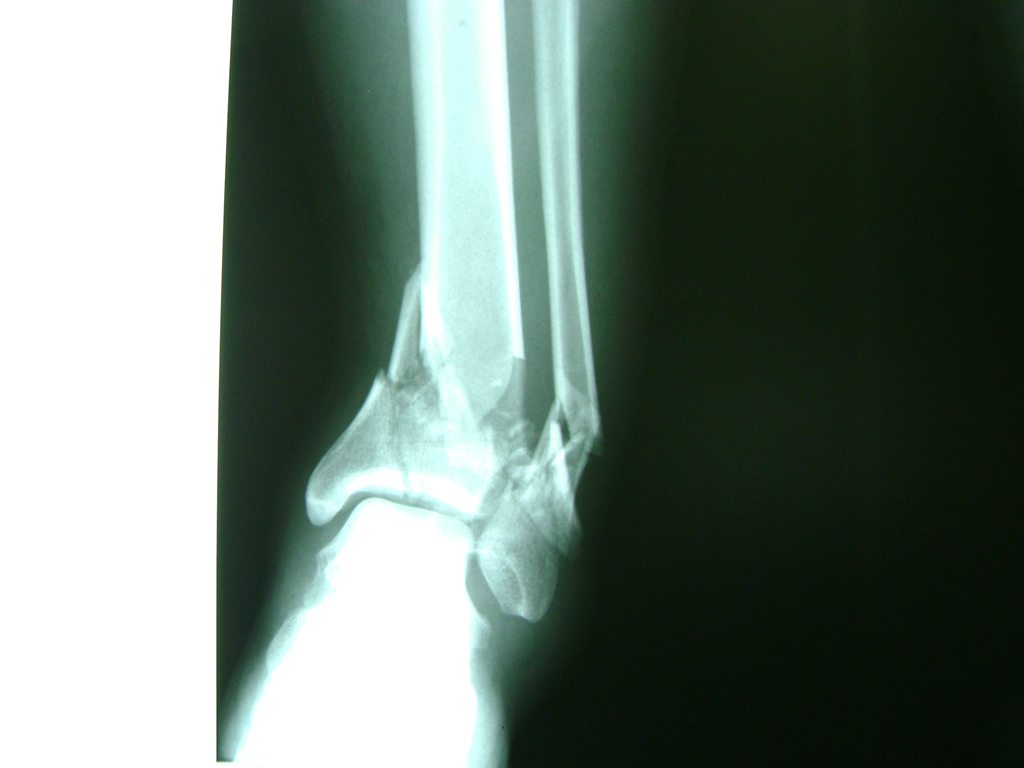

Algunas fracturas de tobillo pueden requerir cirugía si:

- Los extremos de los huesos están desalineados entre sí (desplazados).

- La fractura se extiende hasta la articulación del tobillo (fractura intra-articular).

- Los tendones o ligamentos (tejidos que sujetan los músculos y los huesos entre sí) están rotos.

- El médico cree que sus huesos probablemente no sanen apropiadamente sin cirugía.

- El médico considera que la cirugía puede permitirle una recuperación más rápida y confiable.